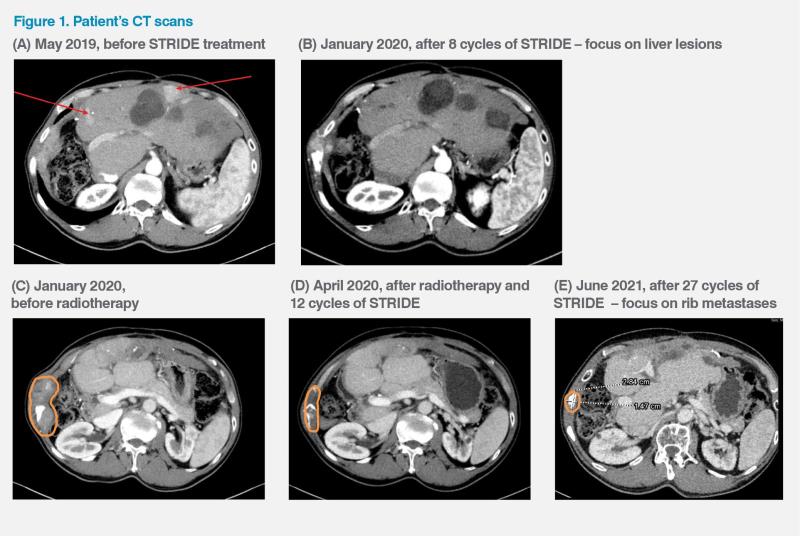

However, in May 2019, the patient developed multifocal HCC and metastasis in one of the right ribs, which caused considerable discomfort. (Figure 1A) His disease was classified as Barcelona Clinic Liver Cancer (BCLC) stage C. He had normal liver function (Child-Pugh class A) and an Eastern Cooperative Oncology Group Performance Status (ECOG PS) of 0. His serum alphafetoprotein (AFP) level was 111 ng/mL. There was no microvascular invasion or lymph node metastasis.

After eight treatment cycles, the patient developed a new palpable bone metastasis in the right rib, but the initial right rib bone metastasis showed response to STRIDE, and in January 2020, all the liver lesions complete resolution or significant shrinkage. (Figure 1B) The newly developed rib metastasis was subsequently treated with radiotherapy while the patient continued to receive durvalumab. Over the next several months, his rib lesions became smaller and the liver lesions remained treated. (Figure 1C–E) His disease eventually went into complete remission in October 2020. However, in March 2024, a new liver recurrence measuring 1.7 cm in the longest dimension was detected. He was given another round of radiotherapy for that lesion and is expected to continue with the STRIDE regimen indefinitely. As of May 2024, the patient had received a total of 59 treatment cycles with the last dose given in April 2024.